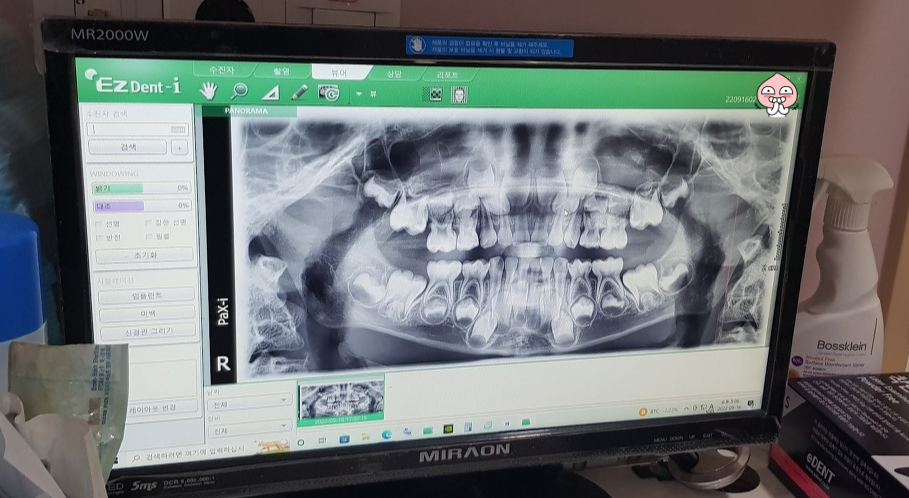

의사 선생님이 이 곳 저 곳을 입을 벌려 보시더니 사진을 찍어보자고 하시네요.

사진을 찍었습니다.

이 사진을 보시더니 5개는 신경치료를 하고 은으로 씌워야 하고 3개는 떼우는 치료를 해야 한다고 하셨습니다.

신경치료는 신경을 죽이는 치료지만 영구치가 나오는데 아무런 문제가 없다고 하셨습니다.

그리고 누운 상태에서 바로 사진을 찍었습니다. 사진상으로 보니 오른쪽 위 어금니가 썩어서 푹 파여 있네요. 그리고 붙어있는 어금니도 같이 썩은 것 같습니다.

이 어금니는 신경치료를 해야하구요. 사진상으로 잘 안보이지만 붙어 있는 어금니도 신경치료를 해야할 것 같습니다. 그리고 은으로 씌울 겁니다. 만약 붙어있는 어금니가 신경치료 안해도 될 정도면 그냥 떼울겁니다.